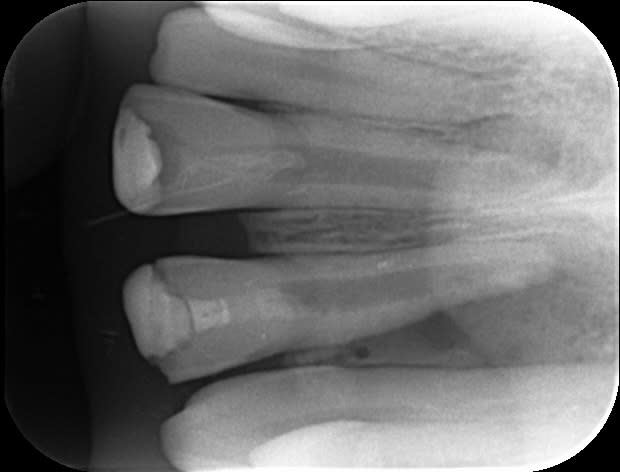

un patient vient me voir avec un compo vieux de plusieurs années sur une 11 (due à un choc il y a 30 ans)

Le compo a vieilli et intéresse un bon tiers de la dent.

La dent ne répond pas au test de vitalité, et la radio confirme l'infection apicale.

j'ai bien entendu prévu de réaliser l'endo, mais l'ouverture de l'apex m'embête...

passage jusqu’à f3, irrigation et inserts us par voie ortho.

cône ajusté (j'ai senti une resistance au retrait).

Il n'y a qu'un seul cône ? quel cône as tu utilisé finalement vu le diamêtre?

2 cônes..

1 f2 coupé et mis à l'envers.

Un f2 dans le bon sens.

Le tout thermocompacte...